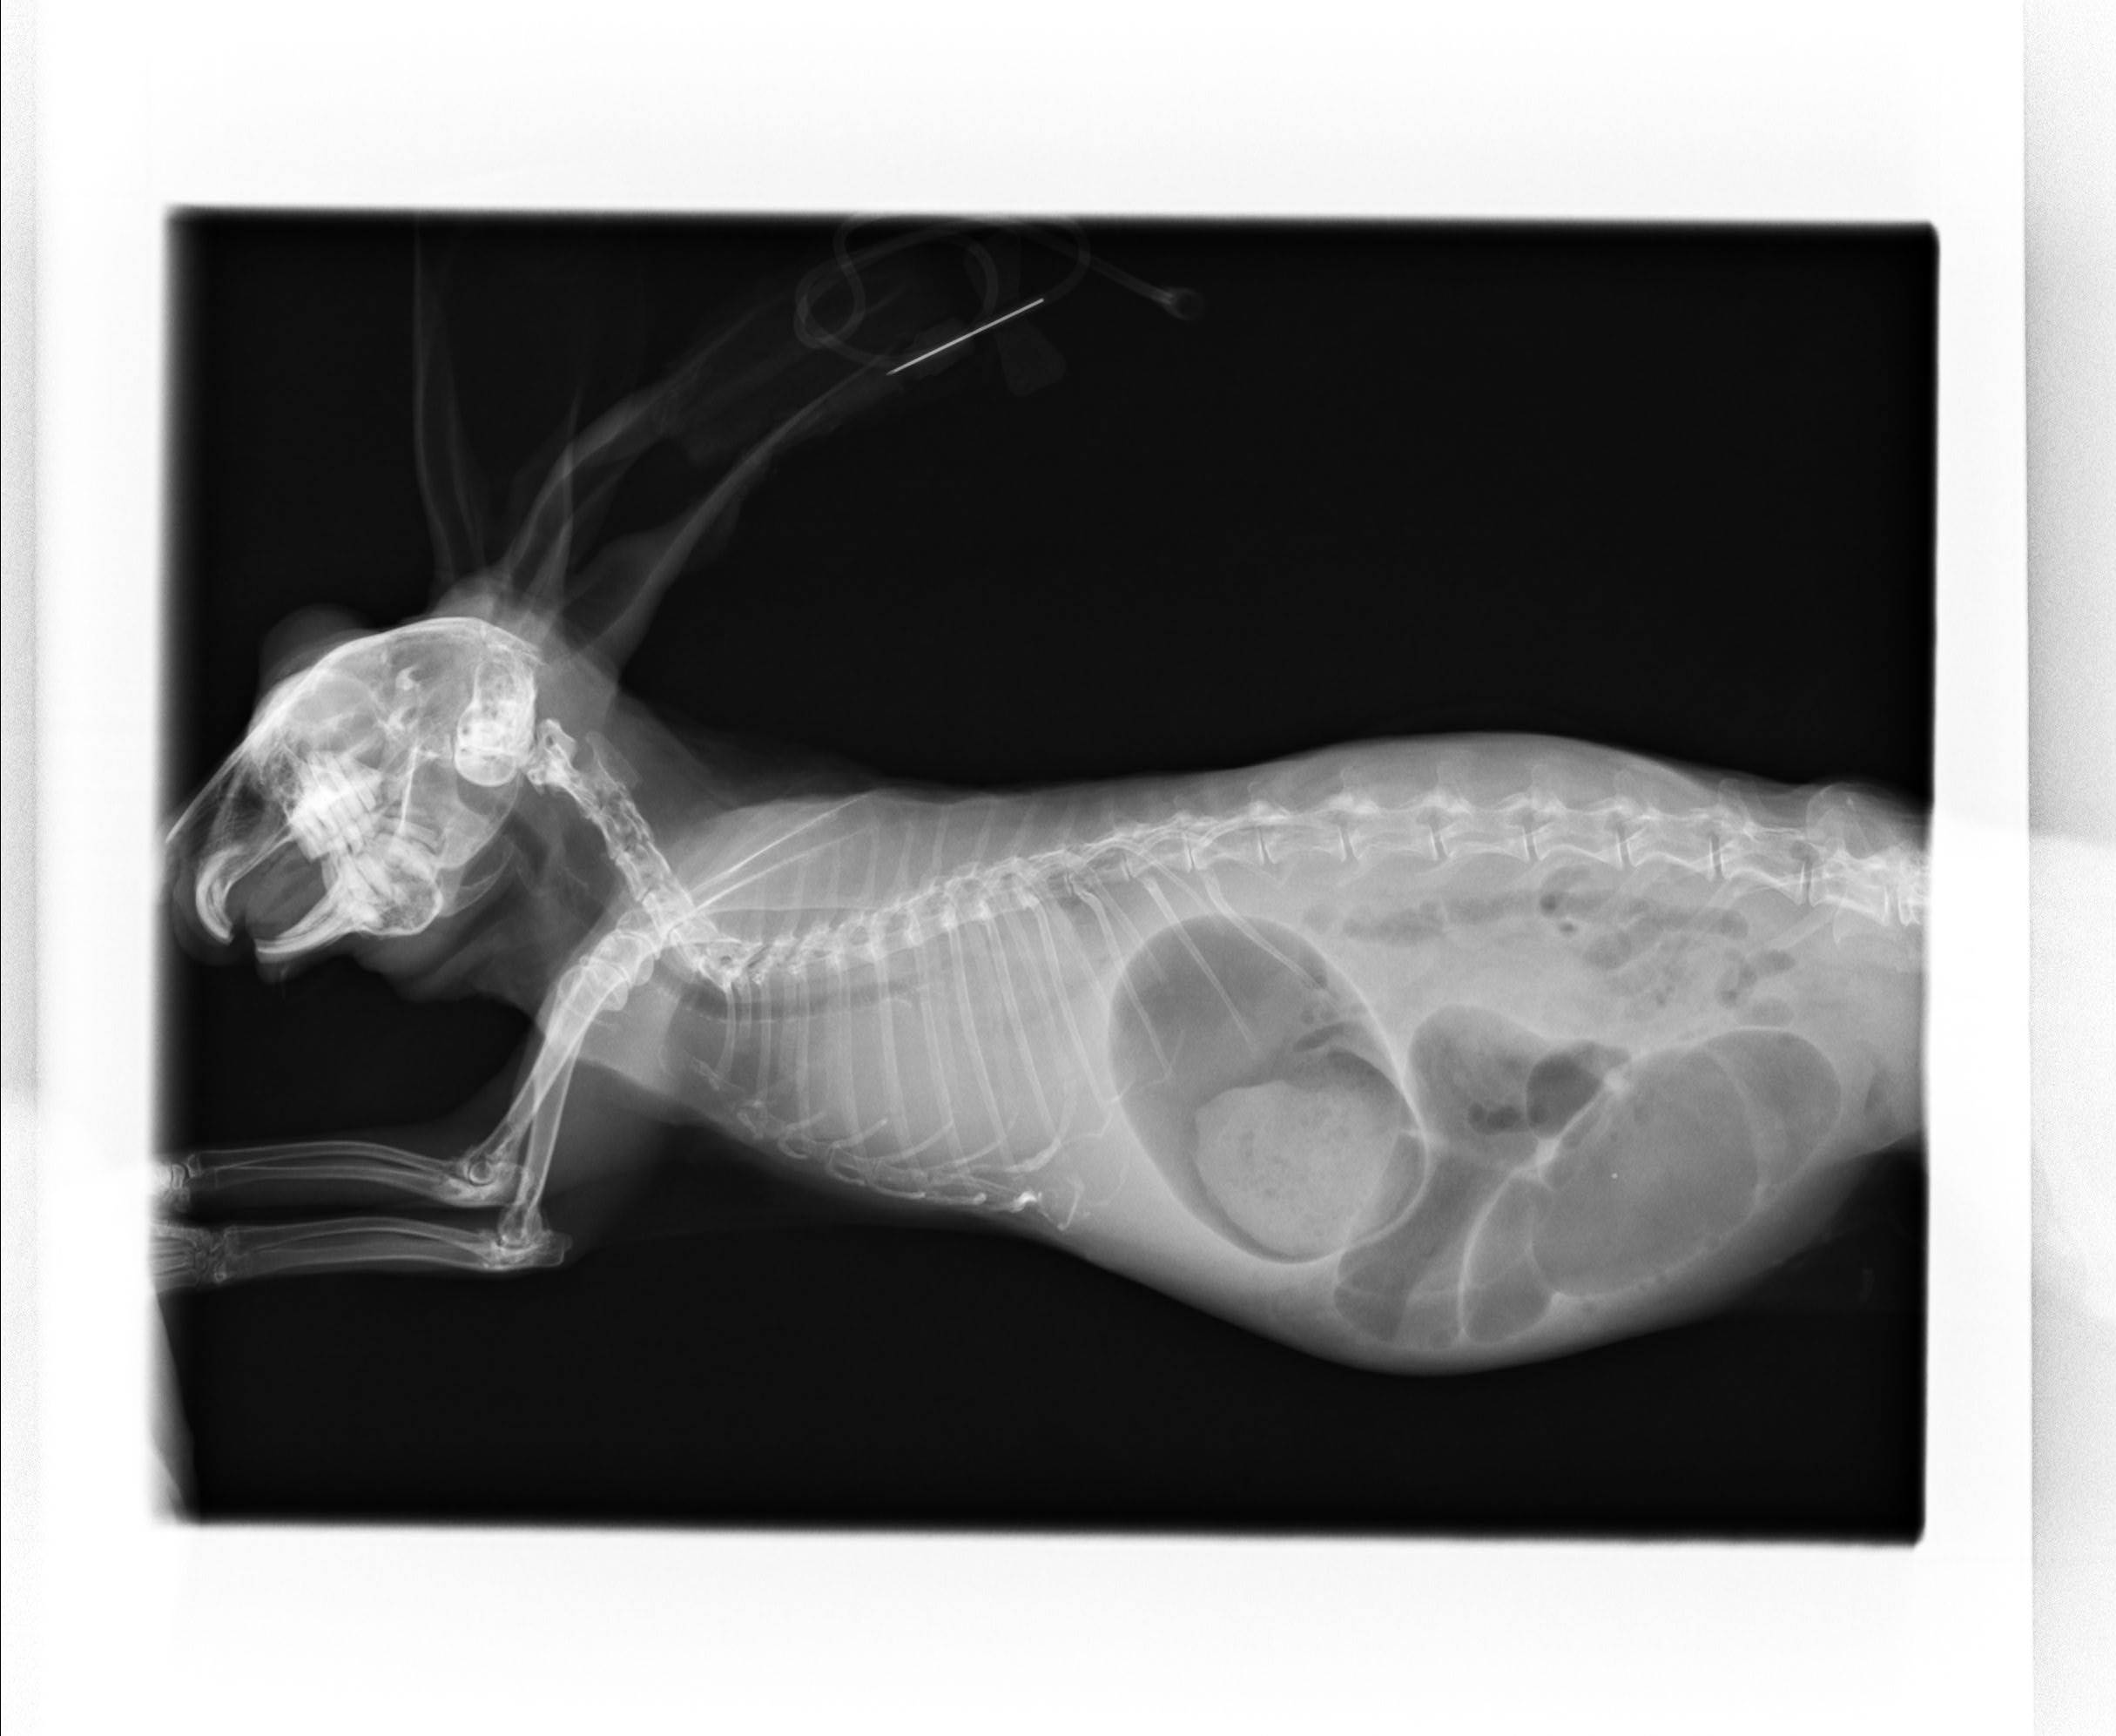

診断は臨床症状に加え、画像検査によって行います。X線検査や超音波検査により胸腔内の腫瘤性病変として認識されることが多いですが、胸腺腫や縦隔リンパ腫との鑑別が困難な場合があります。画像上では境界明瞭な腫瘤として描出されることがあり、単独の画像所見のみでの確定診断は難しいことがあります。必要に応じて細針吸引や生検を行い、細胞診や細菌培養により診断を補助します。

症例:8歳 ホーランドロップ 未避妊メス

3日前から食欲ないとの主訴で来院。検査では腎臓が悪く、肺に腫瘤が認められたため、抗生物質、ステロイドによる治療を行いましたが治療の甲斐なく亡くなってしまいました。この子のヒストリーでは胸腺腫、子宮腺癌の肺転移、肺膿瘍などが考えられましたが、呼吸状態と腎臓も悪く生前に積極的な検査を行うことができませんでしたが、肺の細胞診で肺膿瘍が疑われました。